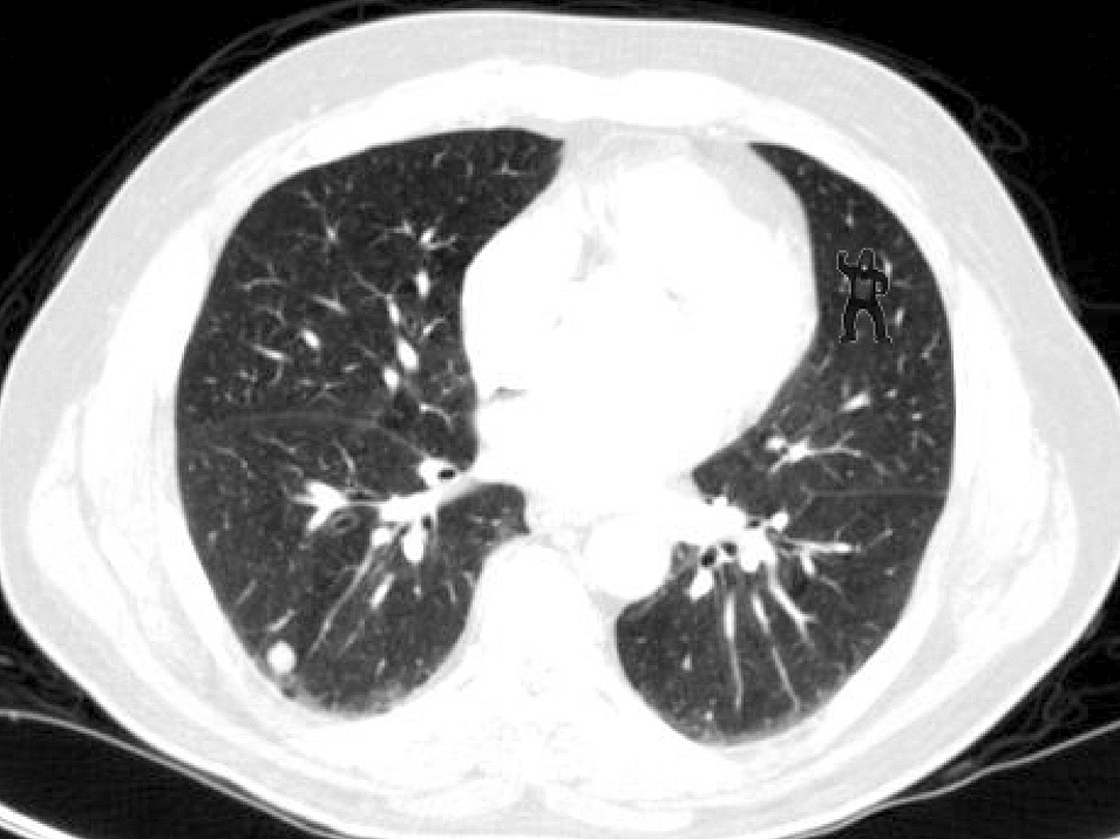

CASO CLÍNICO #30

Na investigação de nódulos pulmonares, 83% dos radiologistas erraram a interpretação dessa tomografia. O que você vê nesse corte tomográfico? Escreva abaixo sua interpretação.

In the investigation of pulmonary nodules, 83% of radiologists were wrong at the assessment of this tomography. What you see at this CT slice? Write below your interpretation.